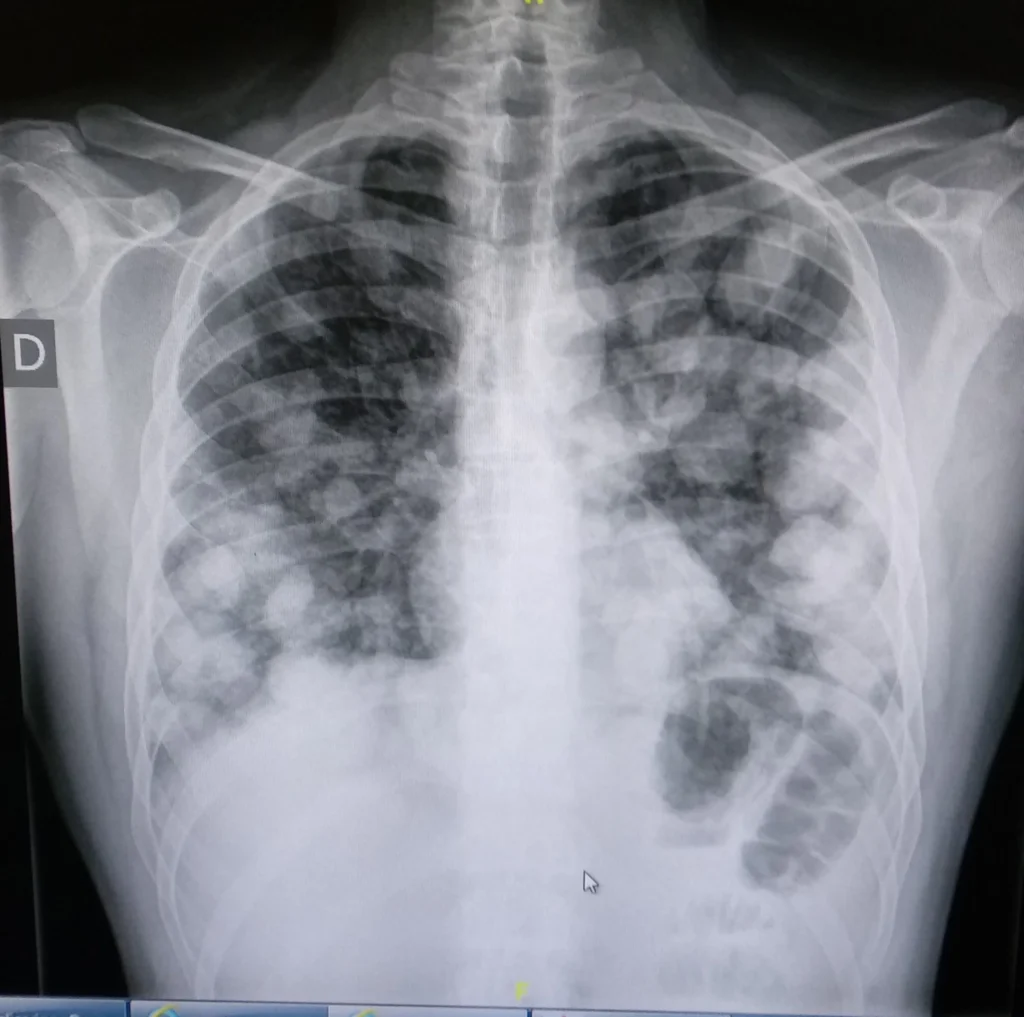

Metástasis pulmonar

Las metástasis pulmonares se desarrollan cuando células malignas originadas en un tumor fuera del pulmón se diseminan hacia este órgano a través de vías vasculares, como las arterias o venas,…